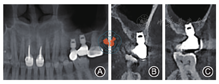

进行Ⅰ期牙种植术时,发现上颌窦颊侧骨质缺损,囊肿侧壁暴露,选择及时去除囊肿也是必要的。林野曾指出上颌窦囊肿因囊液滞留,导致黏膜膨胀而菲薄,术中或术后若黏膜破裂,囊液外溢,可使植骨材料发生感染导致种植失败[9],为避免囊肿影响种植体骨整合和长期临床效果,术者及时抽出囊液,完整摘除囊肿,0.9%氯化钠加庆大霉素彻底冲洗上颌窦,骨缺损处放置PRF膜。尽管术后上颌窦内留存了较多的0.9%氯化钠溶液,但后期修复时上颌窦0.9%氯化钠溶液全部吸收,CBCT显示之前骨缺损处骨壁修复良好(图8),种植体骨结合成功,骨量稳定,囊肿无复发。